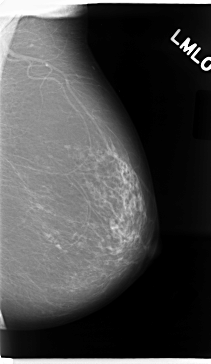

C_0016_1.LEFT_MLO

LEFT_MLO LINES 4720 PIXELS_PER_LINE 2736 BITS_PER_PIXEL 12 RESOLUTION 50 NON_OVERLAY